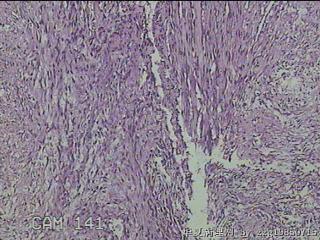

性别

男

年龄

39

临床诊断

左肘部肿物:炎性脂肪瘤

一般病史

发现左肘部肿物1周。

标本名称

左肘部包块

大体所见

灰白粉红色组织2x1.8x0.3㎝一团,表面结节状,光滑,切面灰白粉红色,质软。

纤维组织细胞瘤

有外伤史吗,考虑结节性筋膜炎。

首先考虑结节性筋膜炎。

梭形细胞肿瘤,待免疫组化